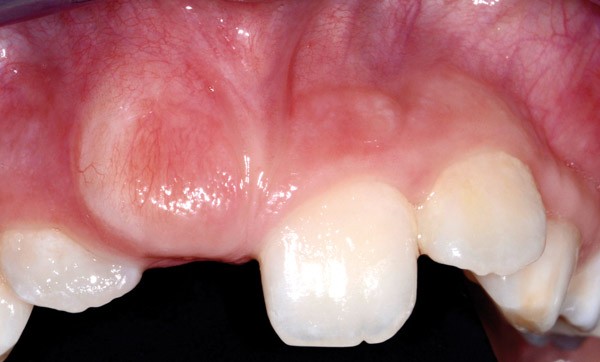

L’inclusion des incisives maxillaires est certes moins fréquente que celles des canines (0,4  % de la population pour les incisives contre 0,8 à 2,8 % pour les canines), mais la prise en charge de celles-ci, surtout pour des raisons esthétiques, est tout aussi importante. Les causes les plus fréquentes d’inclusion des incisives maxillaires sont la présence d’un obstacle, comme par exemple un mésiodens, et les antécédents de traumatismes sur les dents temporaires. Toute différence d’éruption entre deux incisives controlatérales ou tout retard d’éruption des deux incisives doit amener les parents à consulter, et le clinicien à rechercher une éventuelle inclusion. La détection, le diagnostic et la prise en charge nécessitent d’être réalisés rapidement pour éviter les complications. L’arsenal thérapeutique, variable en fonction de la situation clinique, peut inclure l’avulsion de la dent temporaire, et/ou l’élimination de l’obstacle empêchant l’éruption de l’incisive, et/ou la mise en place d’un traitement chirurgico-orthodontique.

Une dent incluse est une dent qui n’a pas fait son apparition sur l’arcade à la date normale d’éruption. Elle peut être intra-osseuse ou sous muqueuse, mais le sac folliculaire est non perforé et entoure la dent. Une dent retenue est une dent immature non présente sur l’arcade à l’âge où elle aurait dû faire son éruption et qui peut devenir incluse en ayant achevé son édification radiculaire.